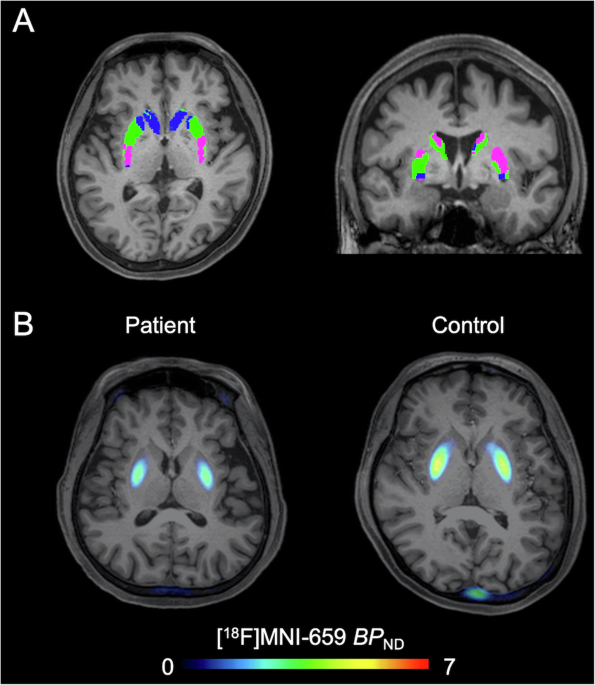

The primary objective of the study was to assess whether striatal PDE10A availability was altered in patients with BD-I compared to healthy controls and to examine the relationship between these alterations and the clinical characteristics of BD-I. This was achieved using positron emission tomography (PET) scans with a radioligand that binds to PDE10A, providing a detailed view of its availability in different regions of the brain.

We focused on the striatum, a brain region known for its involvement in regulating mood, cognition, and motor control. The study included 25 patients diagnosed with BD-I and 27 age- and sex-matched healthy controls. Importantly, most of the BD-I patients were in a euthymic state, meaning they were not currently experiencing manic or depressive episodes, allowing the researchers to focus on trait-related changes rather than state-dependent effects.

The key finding was that patients with BD-I had significantly lower PDE10A availability in two subregions of the striatum: the executive and sensorimotor areas. The executive subregion, in particular, showed a strong correlation between reduced PDE10A levels and a higher number of mood episodes in the past year. This suggests that diminished PDE10A activity in this area could be linked to a greater risk of recurrent mood episodes, making it a critical area of focus for future research.